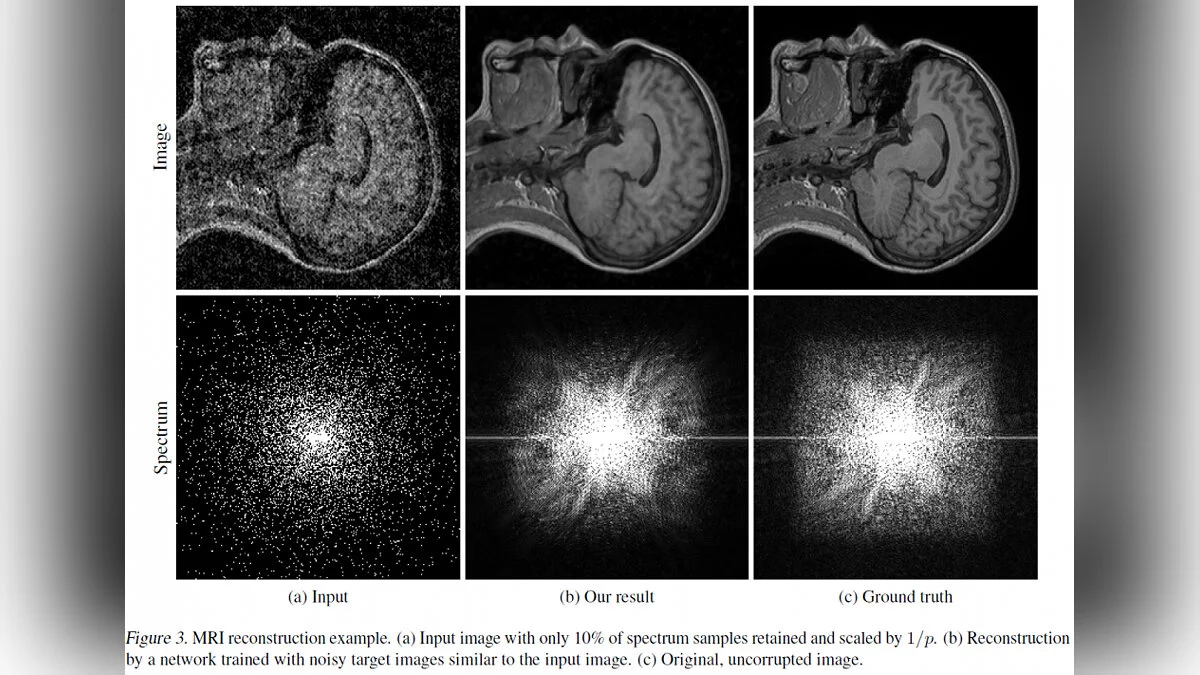

Этот метод можно использовать не только на шумных фотографиях, но и для улучшения изображений МРТ или данных с телескопов.